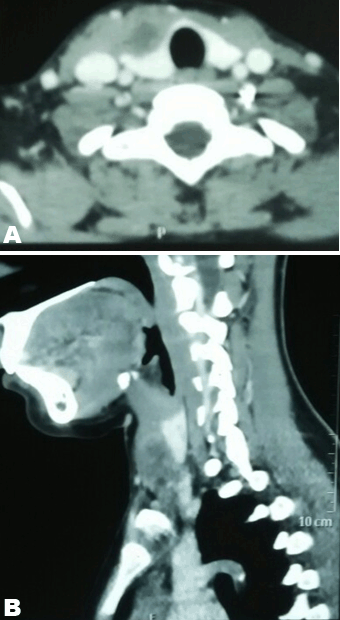

A 16-year-old girl presented with swelling in the right lobe of thyroid. There were no generalized symptoms like fever, malaise, night sweats and weight loss. There was no history of difficulty in deglutition or voice change. On clinical examination there was a single abscess of size 4x4 cm in right lobe of thyroid moving with deglutition. The margins were well demarcated, smooth surface, non-tender and overlying skin was normal with a tattoo mark on it (Figure 1). There were no clinical features of hypothyroidism or hyperthyroidism. Routine blood investigations were done; hemoglobin 11.0 g/dl, total leucocytes count 8600/mm3, neutrophils 67/mm3, lymphocytes 31/mm3 and eosinophils 2/mm3. The erythrocyte sedimentation rate was 20 mm. The Mountax test was highly positive more than 10 mm in diameter. Thyroid function tests T3, T4, TSH were normal. X-ray chest was normal. Ultrasonography of neck revealed a 50x45x20 mm solitary nodule in the right lobe of liver. This solitary thyroid nodule was showing thick irregular wall with central necrosis reported as suspected thyroid abscess. Magnetic resonance imaging scan of the neck showed a lesion of intermediate signal intensity due to presence of dense inflammatory cells and granulomas with central necrosis (Figure 2). A doubt about carcinoma of thyroid was placed as differential diagnosis. The CECT scan of neck was done to rule out carcinoma of thyroid gland. This was helpful in diagnosis of tubercular thyroid abscess as localized caseous lesion in right lobe of thyroid (Figure 3). Fine needle aspiration from this solitary thyroid nodule was done to confirm the diagnosis. The stained smears revealed degenerated and intact neutrophils, and macrophages in serofibrinous background. A few epithelioid granuloma and multinucleated giant cells are also seen suggestive of tuberculosis with central caseous necrosis. Ziehl–Neelsen staining with 20% H2SO4 was noncontributory (Figure 4). From the central part of swelling about 2 ml of thick yellow color pus was aspirated as shown in Figure 5. The smears prepared from this pus did not show any acid-fast bacilli. After aspiration the swelling decreased in size. The cytological diagnosis of tubercular abscess was made. The patient was put on antitubercular treatment with four drug regimens. The swelling decreased in size in next three months (Figure 6). She was asked to continue on three drug regimens for another six months leading to complete resolution of swelling. | ||||||